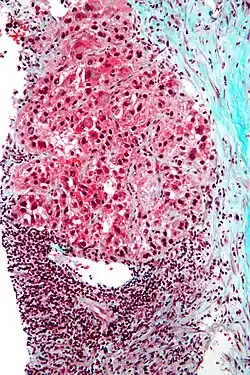

Micrograph showing a Mallory body with the characteristic twisted-rope appearance (centre of image - within a ballooning hepatocyte). H&E stain.

Mallory bodies are highly eosinophilic and thus appear pink on H&E stain. The bodies themselves are made up of intermediate cytokeratin 8/18 filament proteins that have been ubiquitinated, or bound by other proteins such as heat shock proteins, or p62/Sequestosome 1.[5]